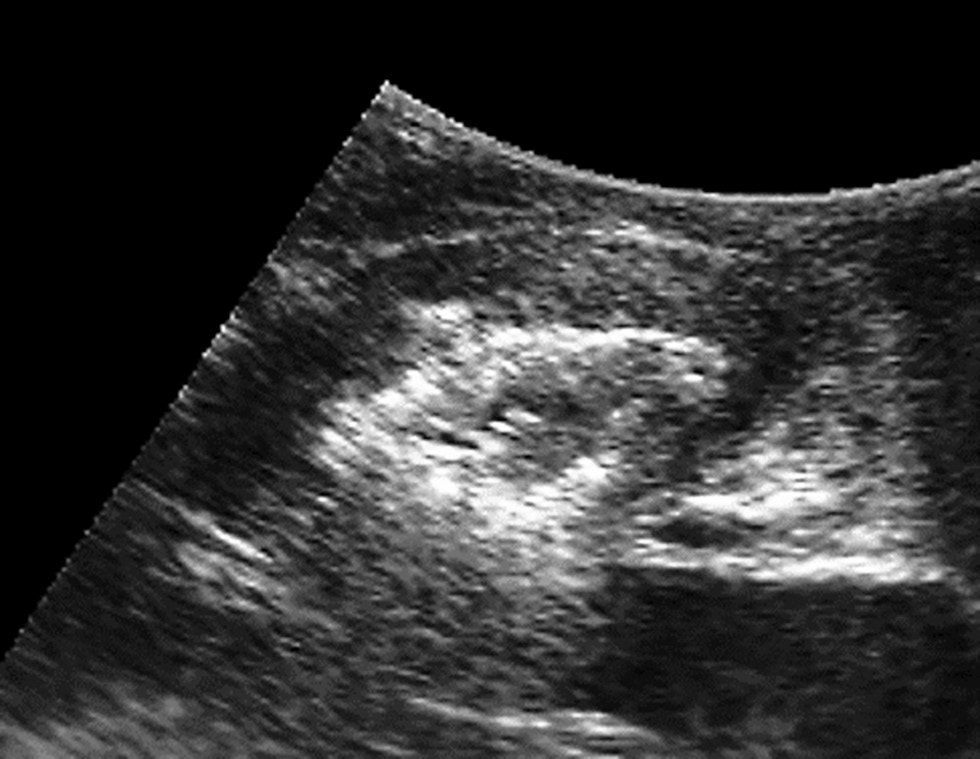

An ultrasound examination of women with grade 1 SPD showed no changes in the pubic symphysis except for diastasis. In addition to diastasis, typical inflammatory symptoms were found in 83.3% (20) of women with grades 2 and 3 SPD. A heterogeneous symphysis with hypoechoic inclusions and an irregular contour was reported, with a total of 50% structural changes (p < 0.05) (Fig. 1).

Fig. 1. Echogram of the patient’s symphysis pubis in the sagittal plane.

It should be noted that ultrasound showed pubic symphysis diastasis in 28% (14) of women in the control group, including 85.7% (12) of women with grade 1 SPD and 14.3% (2) of women with grade 2 SPD. However, no clinical symptoms were identified, such as pain or an abnormal gait. Therefore, the symphysis width in normal cases and in grade 1 SPD falls within the margin of error of ultrasound measurements, which are an unreliable parameter for assessing tissue changes and insufficient for diagnosing SPD. In addition, pain is not always associated with SPD due to the increased tension in the ligaments and muscles that occurs during the third trimester.